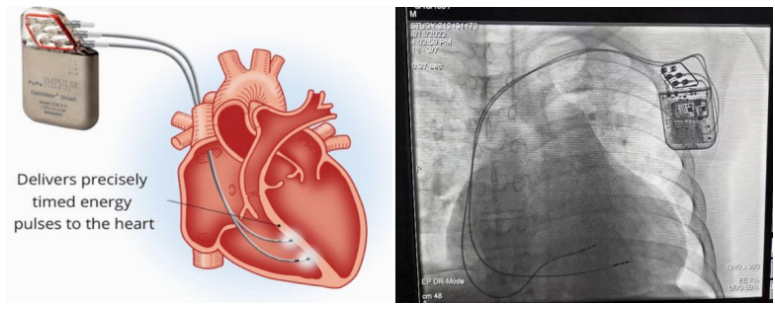

②心臟再同步治療

Cardiac Resynchronization Therapy,CRT

心臟再同步化治療,指雙心室起搏器,是通過(guò)雙心室同步起搏的方式,幫助心衰患者實(shí)現(xiàn)正常起搏的裝置。CRT包括一個(gè)口袋大小的脈沖發(fā)生器和三根電極導(dǎo)線,可被植入人體。通過(guò)監(jiān)測(cè)心律,在發(fā)現(xiàn)異常后,信號(hào)發(fā)生器發(fā)送電流脈沖,刺激心室重新同步,從而改善癥狀,提高患者的心臟泵血效率。目前有兩種類型的CRT裝置:植入式心臟再同步治療起搏器(CRT-P)和植入式心臟再同步治療除顫器(CRT-D)。主要區(qū)別在于后者除了改善心臟收縮同步性外,還具備除顫功能,能及時(shí)處理危及生命的室性心律失常,避免猝死。